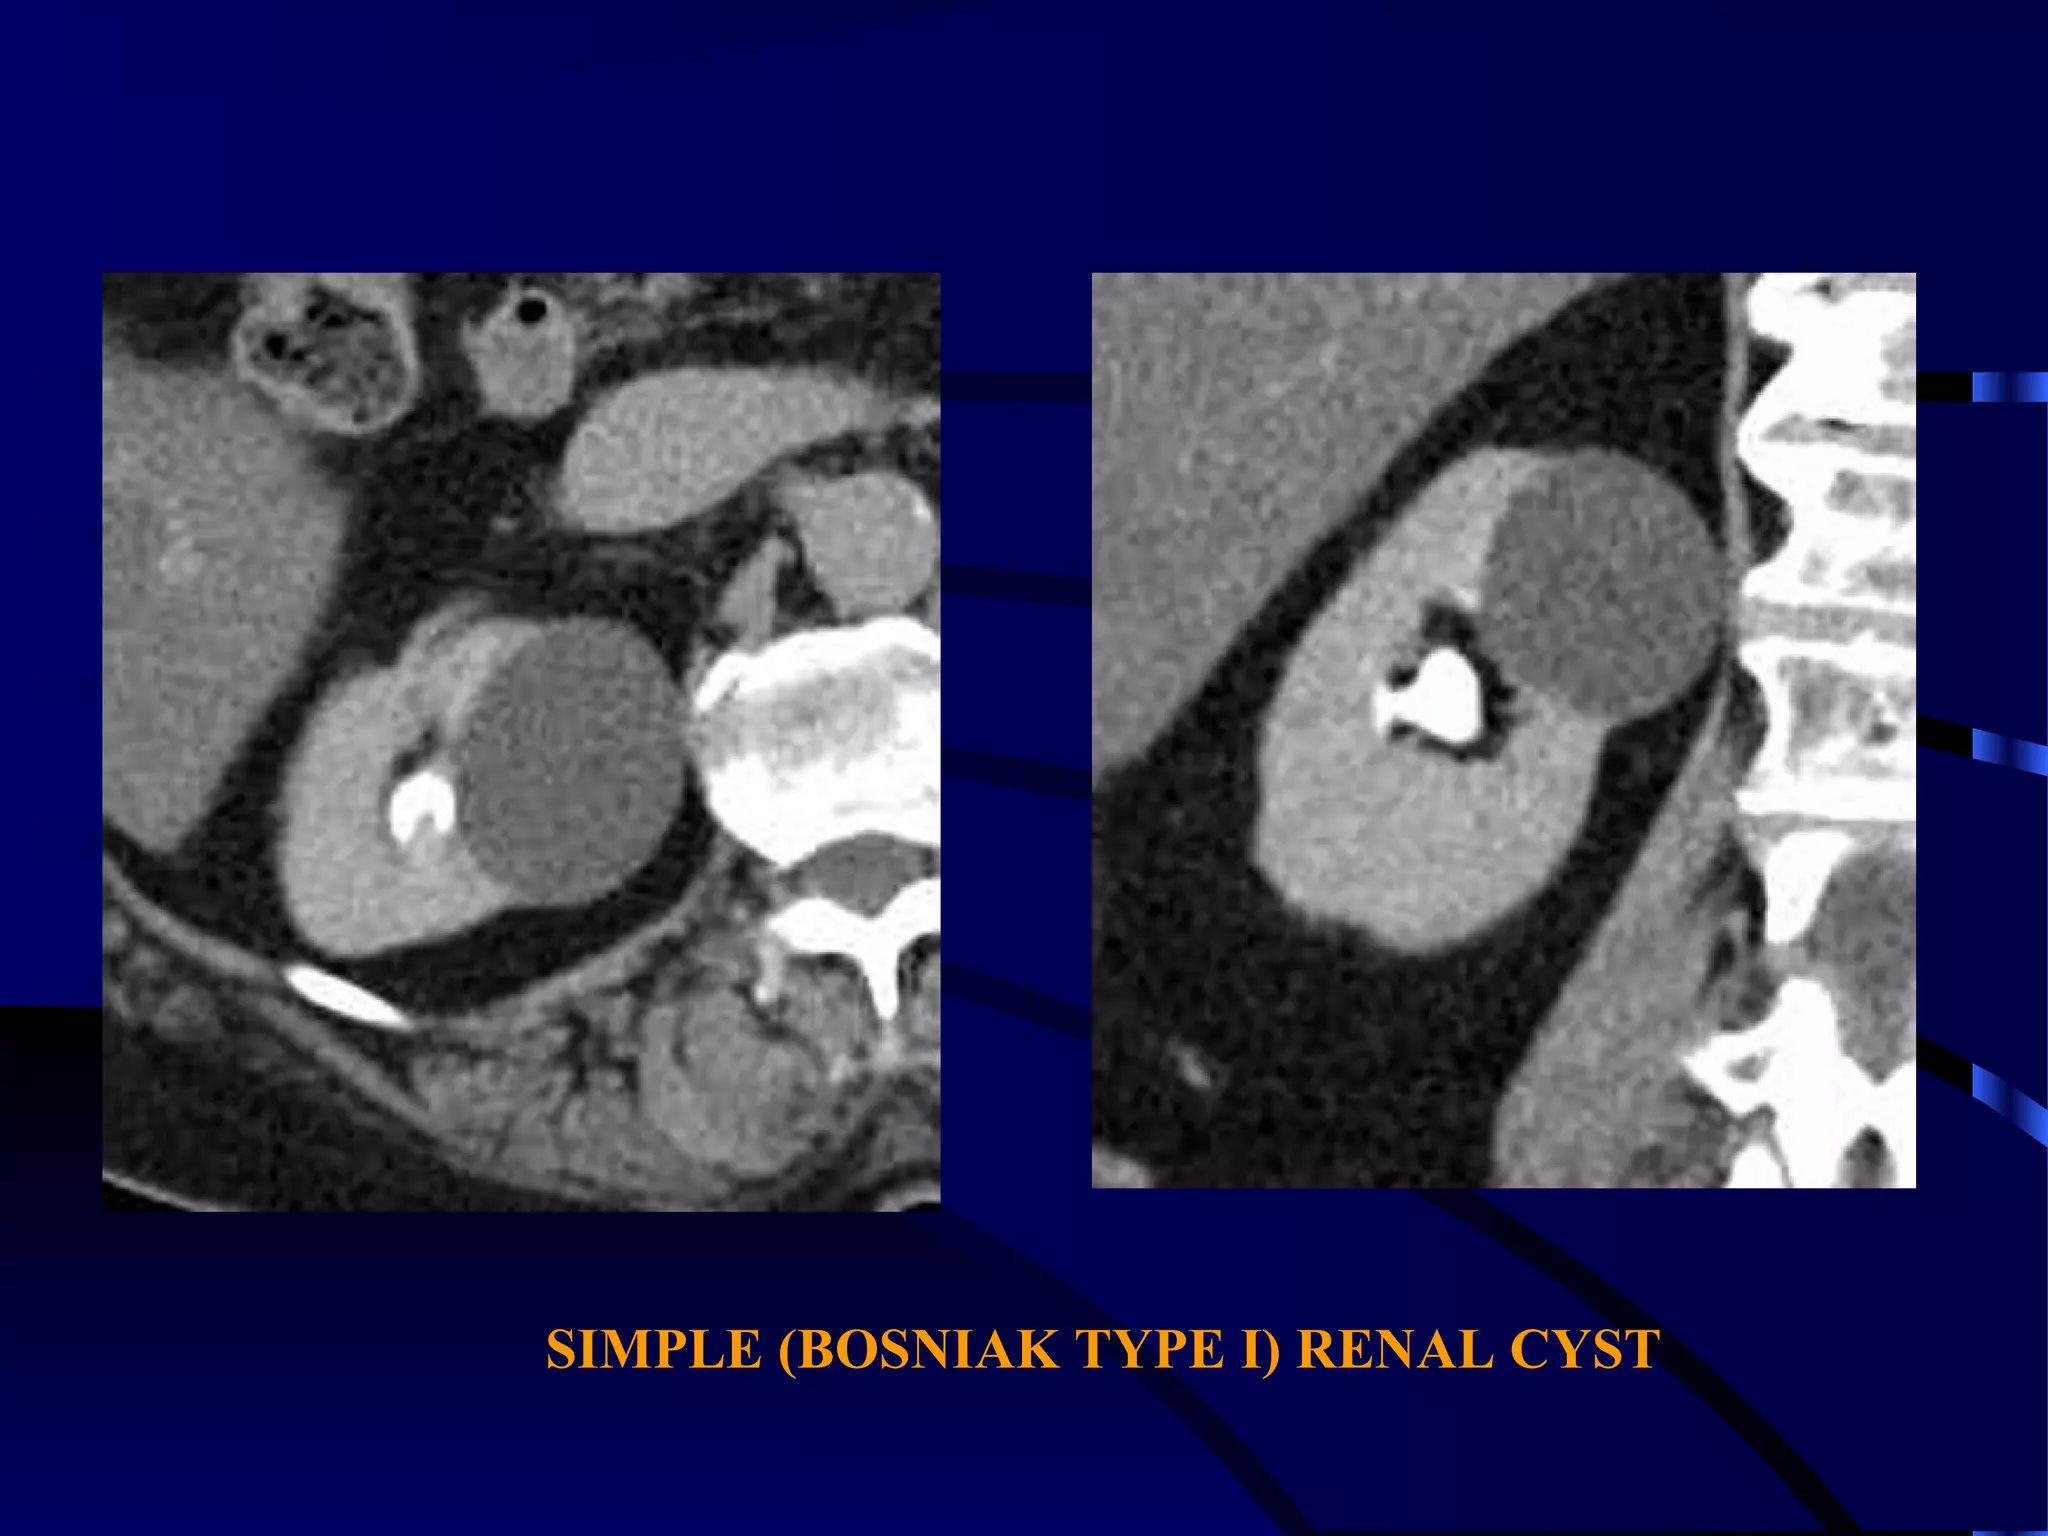

SIMPLE (BOSNIAK TYPE I) RENAL CYST